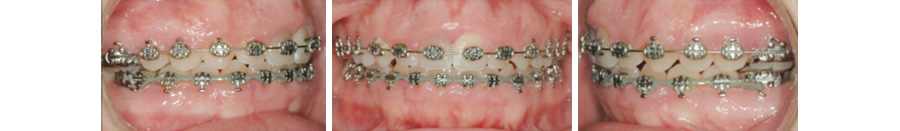

Occlusion acceptable avant le début de l’intrusion orthodontique à l’aide de mini-vis d’ancrage

Mécanique orthodontique utilisée pour faire l’ingression du maxillaire supérieur. 4 mini-vis ont servi d’ancrage temporaire pour la mécanique visant é intruder le dentition maxillaire.

• (E) Occlusion au début du traitement.

• (F) Occlusion à la fin du traitement.